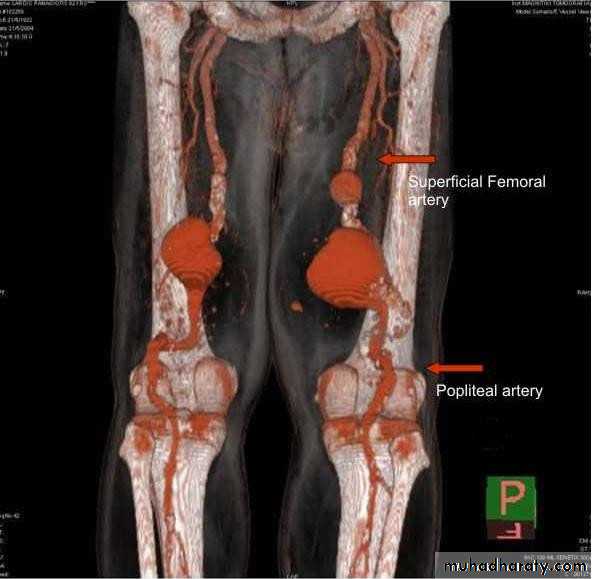

Femoral aneurysm

Popliteal aneurysm